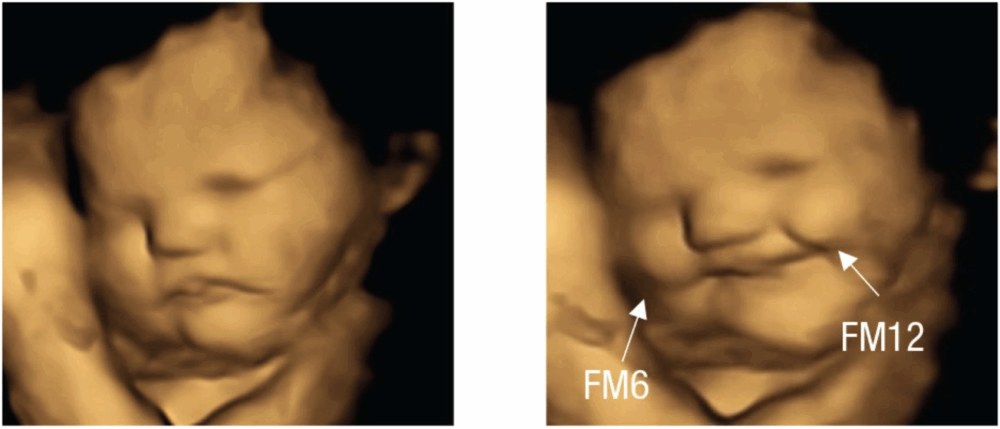

El resultado de las ecografías 4D de 100 mujeres embarazadas para ver cómo respondían sus bebés en el útero después de haber estado expuestos a los sabores de los alimentos consumidos por sus madres, fue de lo mas sorprendente: los bebés en el útero sonreían poco después de que sus madres comieran zanahorias, pero hacían muecas de disgusto cuando optaban por la col rizada.

Para el experimento, a las gestantes se les pidió no ingerir alimentos en la hora previa a su cita. Luego, a cada madre se le dio una cápsula que contenía sabor a zanahorias o col rizada. Una cápsula contenía aproximadamente 400 miligramos de polvo de zanahoria o 400 miligramos de polvo de col rizada. También hubo un grupo de control, que estaba formado por madres que no ingirieron ninguna de las cápsulas. En total, 100 madres de entre 18 y 40 años participaron en el estudio. Cuando la madre consumía una cápsula de zanahoria, los fetos adoptaban una expresión similar a la risa con el doble de frecuencia que cuando la madre tragaba una cápsula de col rizada o ninguna cápsula. Así, los movimientos como levantar el labio superior, bajar el labio inferior, presionar los labios y una combinación de estos, que sugieren una cara llorando, fueron mucho más comunes en el grupo de la col rizada que en los otros grupos.